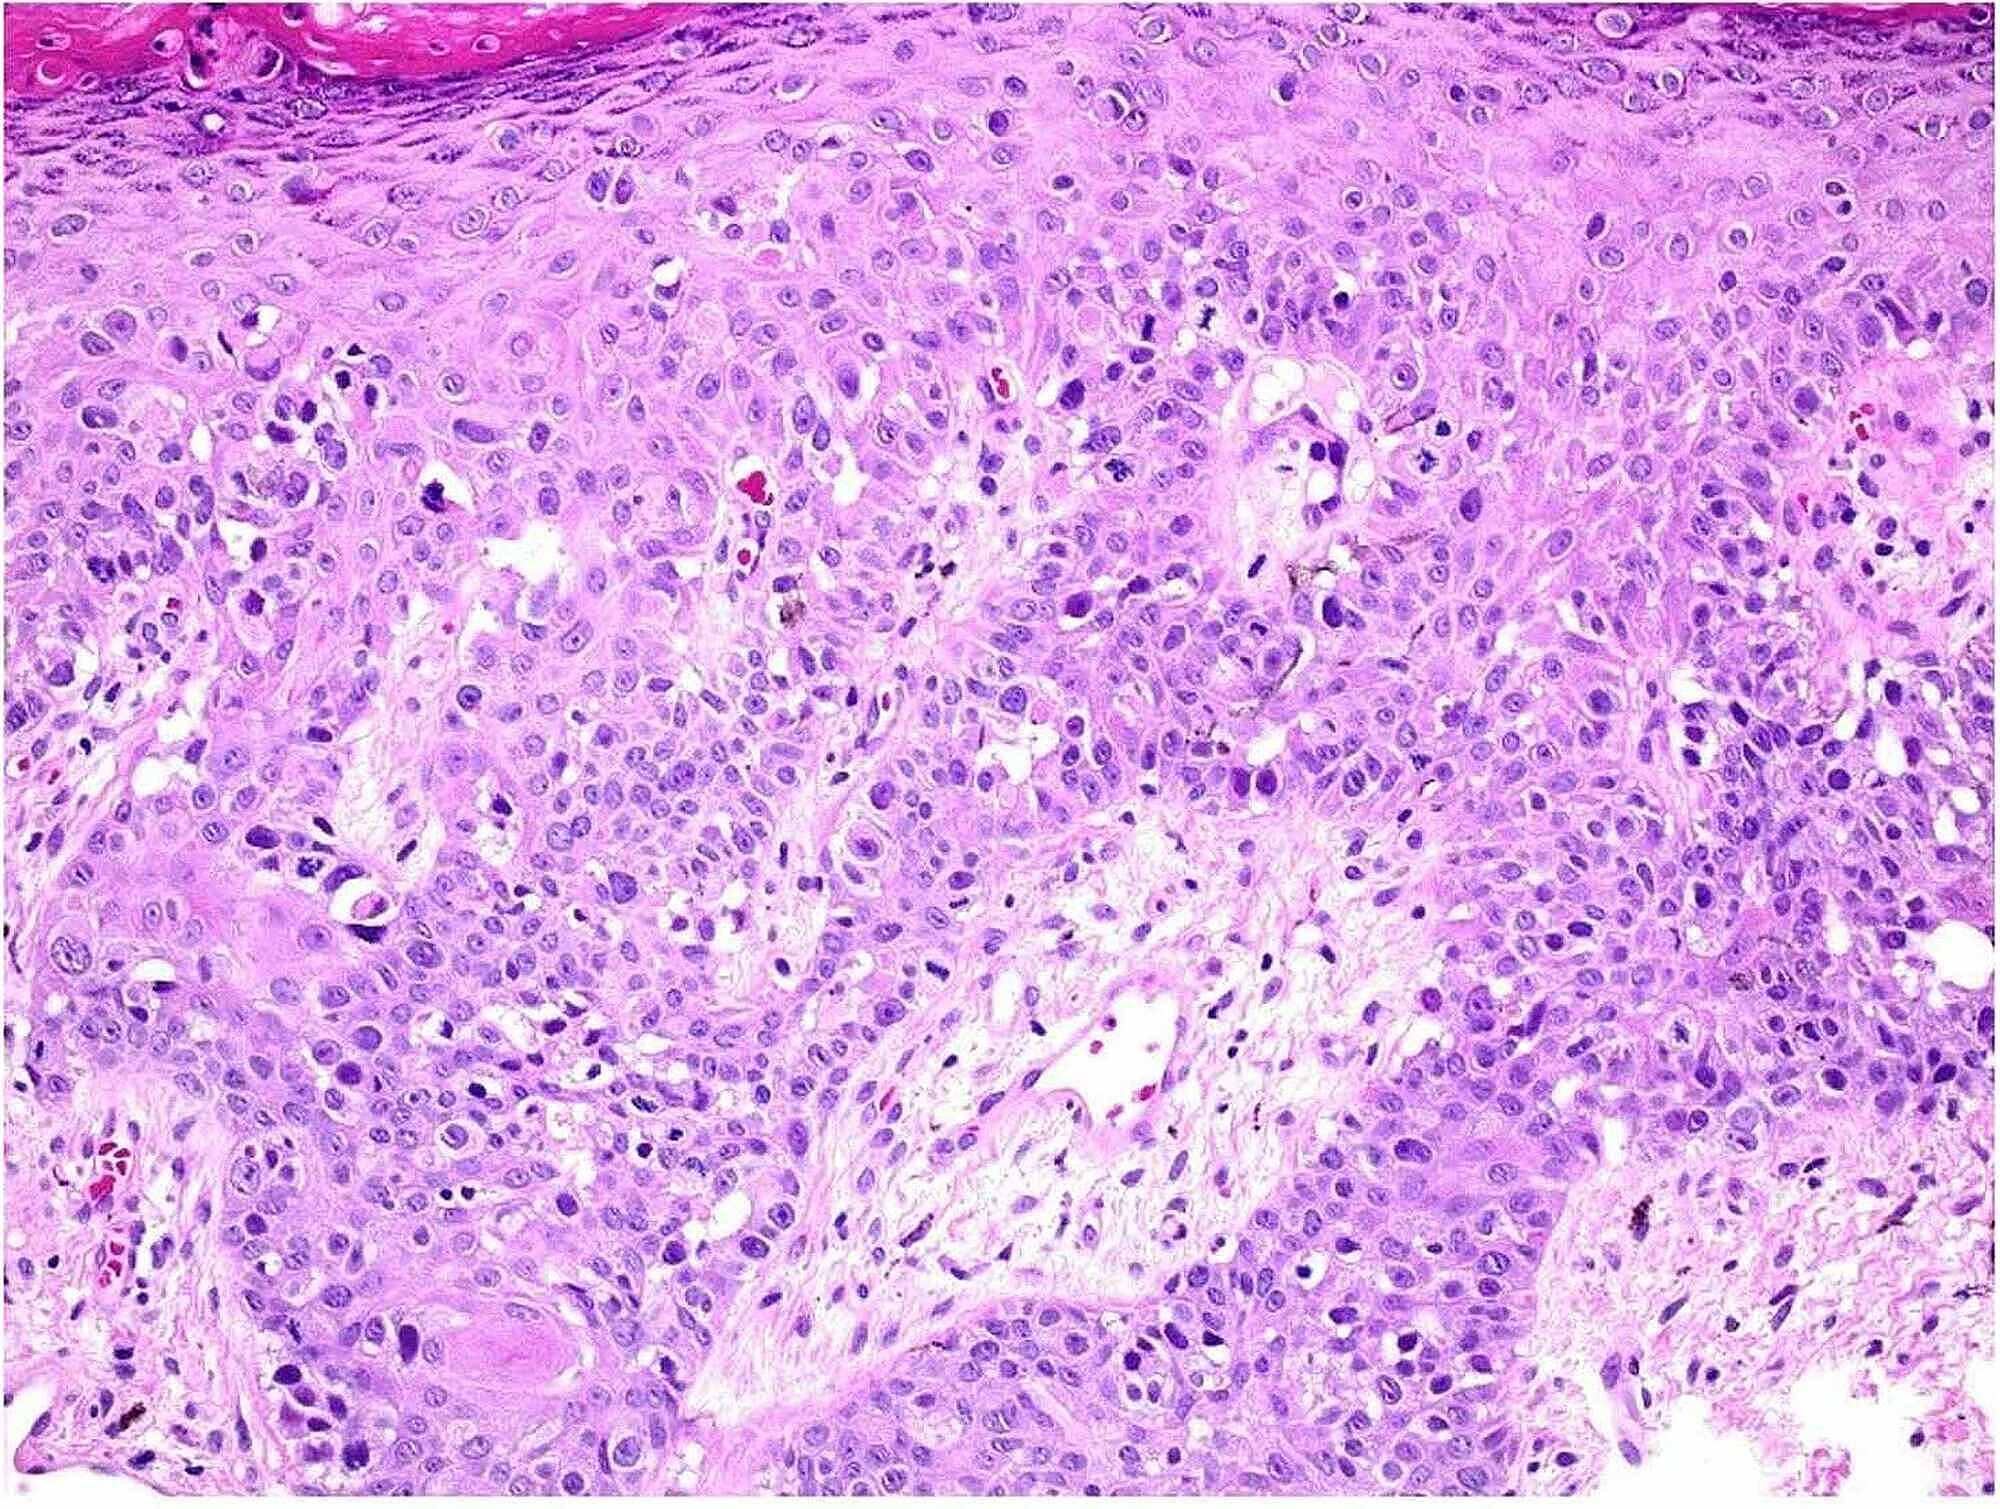

Cureus Extensive Extramammary Paget’s Disease With Underlying

From www.cureus.com

Extensive Extramammary Paget’s Disease With Underlying Perianal Paget's Disease Radiation Therapy This systematic review investigates the role of radiotherapy and its best technical profile in the treatment of this disease, with great attention. Radiotherapy was administered as postoperative adjuvant treatment in 9 articles with doses ranging between 32 and 64.8 gy in 20 to 30. [1] complete surgical removal of localized disease. Sir james paget described an intraepidermal neoplasm of the. Paget's Disease Radiation Therapy.

Cureus Extensive Extramammary Paget’s Disease With Underlying Paget's Disease Radiation Therapy Sir james paget described an intraepidermal neoplasm of the mammary areola in 1874, and it was subsequently named paget's disease (1). This systematic review investigates the role of radiotherapy and its best technical profile in the treatment of this disease, with great attention. Extramammary paget's disease (empd) is a relatively rare malignancy, and there are few reports related to radiation. Paget's Disease Radiation Therapy.

Cureus Extensive Extramammary Paget’s Disease With Underlying Paget's Disease Radiation Therapy Radiotherapy was administered as postoperative adjuvant treatment in 9 articles with doses ranging between 32 and 64.8 gy in 20 to 30. Extramammary paget's disease (empd) is a relatively rare malignancy, and there are few reports related to radiation therapy. When invasive extramammary paget disease (empd) metastasizes to distant sites as well as in case of wide locoregional disease that. Paget's Disease Radiation Therapy.